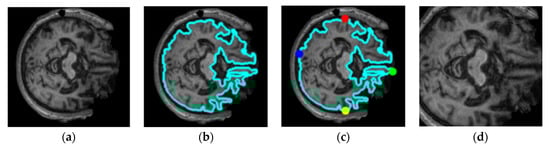

3.1. Dataset Pre-Processing